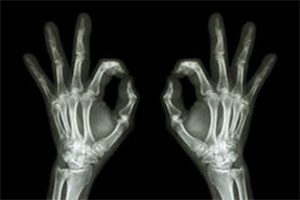

rok 1896

Wykonano w Ameryce zdjęcie rentgenowskie. Z rewolweru postrzelono rękę nieboszczyka, a zdjęcie pokazało dokładne umiejscowienie kuli.